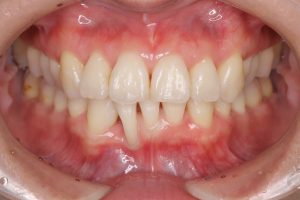

口腔内を確認すると、全体的に歯肉は炎症を起こして腫れており、下顎前歯の歯肉には著しい退縮を認めました。

歯周組織検査を行うと、30代にもかかわらず、中等度から重度の歯周ポケットを多数認めました。

治療は、担当する歯科衛生士と連携を取りながら、SRP・むし歯治療・咬合調整・舌側に転位している右下2番(前歯)の抜歯・右下3番(犬歯)の近心スペース改善のダイレクトボンディング・ホームホワイトニング等を行いました。